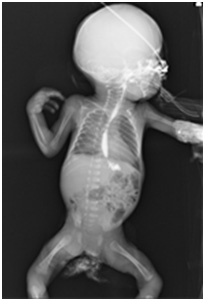

A female newborn weighing 860 gm was delivered by spontaneous vaginal delivery at 26 weeks of gestation. The baby cried immediately after birth and was shifted to a tertiary care hospital NICU for further management, where she received initial supportive care. On Day 17 of life, after insertion of 5 French orogastric tube, the baby’s condition suddenly worsened, and she developed recurrent episodes of apnea requiring mechanical ventilation. A chest radiogram showed the orogastric tube in the right pleural space with a right sided pleural effusion [Table/Fig-1a] . On all previous radiographs, the orogastric tube had been properly positioned. The orogastric tube was removed and a new 5 Fr orogastric tube was reinserted and positioned appropriately, and confirmed both clinically and radiologicaly. The patient was thereafter managed conservatively with no further complications. A radiological dye study was performed 8 days later which showed no leak in esophagus [Table/Fig-1b] , and the baby was gradually weaned off respiratory support. Feeds were reintroduced & gradually increased to full feeds, which were well tolerated, and she was discharged on Day 74 of life.

A radiological dye study performed 8 days later shows no leak in esophagus